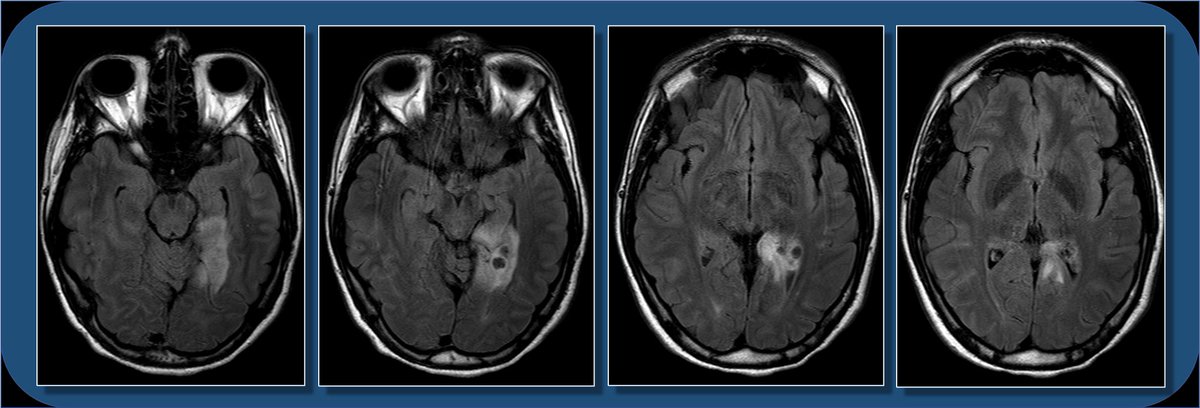

18yoF with seizures. The FLAIR images show focal cortical expansion with cystic components, suggesting a cortically based tumor.

T1 images show mild T1 hypointense mass with cystic components, and minimal if any enhancement. So what’s the differential for a cortically based tumor in a child or young adult who presents with seizure? Pathology following resection c/w ganglioglioma.

Ddx for cortically based tumors in child/young adult includes oligodendroglioma (usually middle-aged adults, often with Ca++), DNET (bubbly, uncommon enhancement), PXA (prominent nodular enhancement), and astrocytoma (usually low grade). Encephalitis can also look similar.

This is less likely to be a glioblastoma, which is usually centered in supratentorial WM, with thick peripheral enhancement, and centrally necrotic.

This location can be a bit difficult to describe if you aren’t up on gyral anatomy. Is it med temporal lobe? occipital lobe? limbic? Describing gyral location is more precise, can explain expected symptoms, and clue in future surgical approach.

The lingual gyrus is involved in holistic visual and word processing, encoding visual memories, imagery, and dreaming. The ganglioglioma in the shown case is centered in the lingual gyrus.

Cingulate g. is part of the limbic circuit; the post cingulate cortex (PCC) is important in default mode network, awareness, pain, and episodic memory retrieval. PCC including the retrosplenial cortex (which together some call restrosplenial gyrus) is involved by the tumor. 11/13